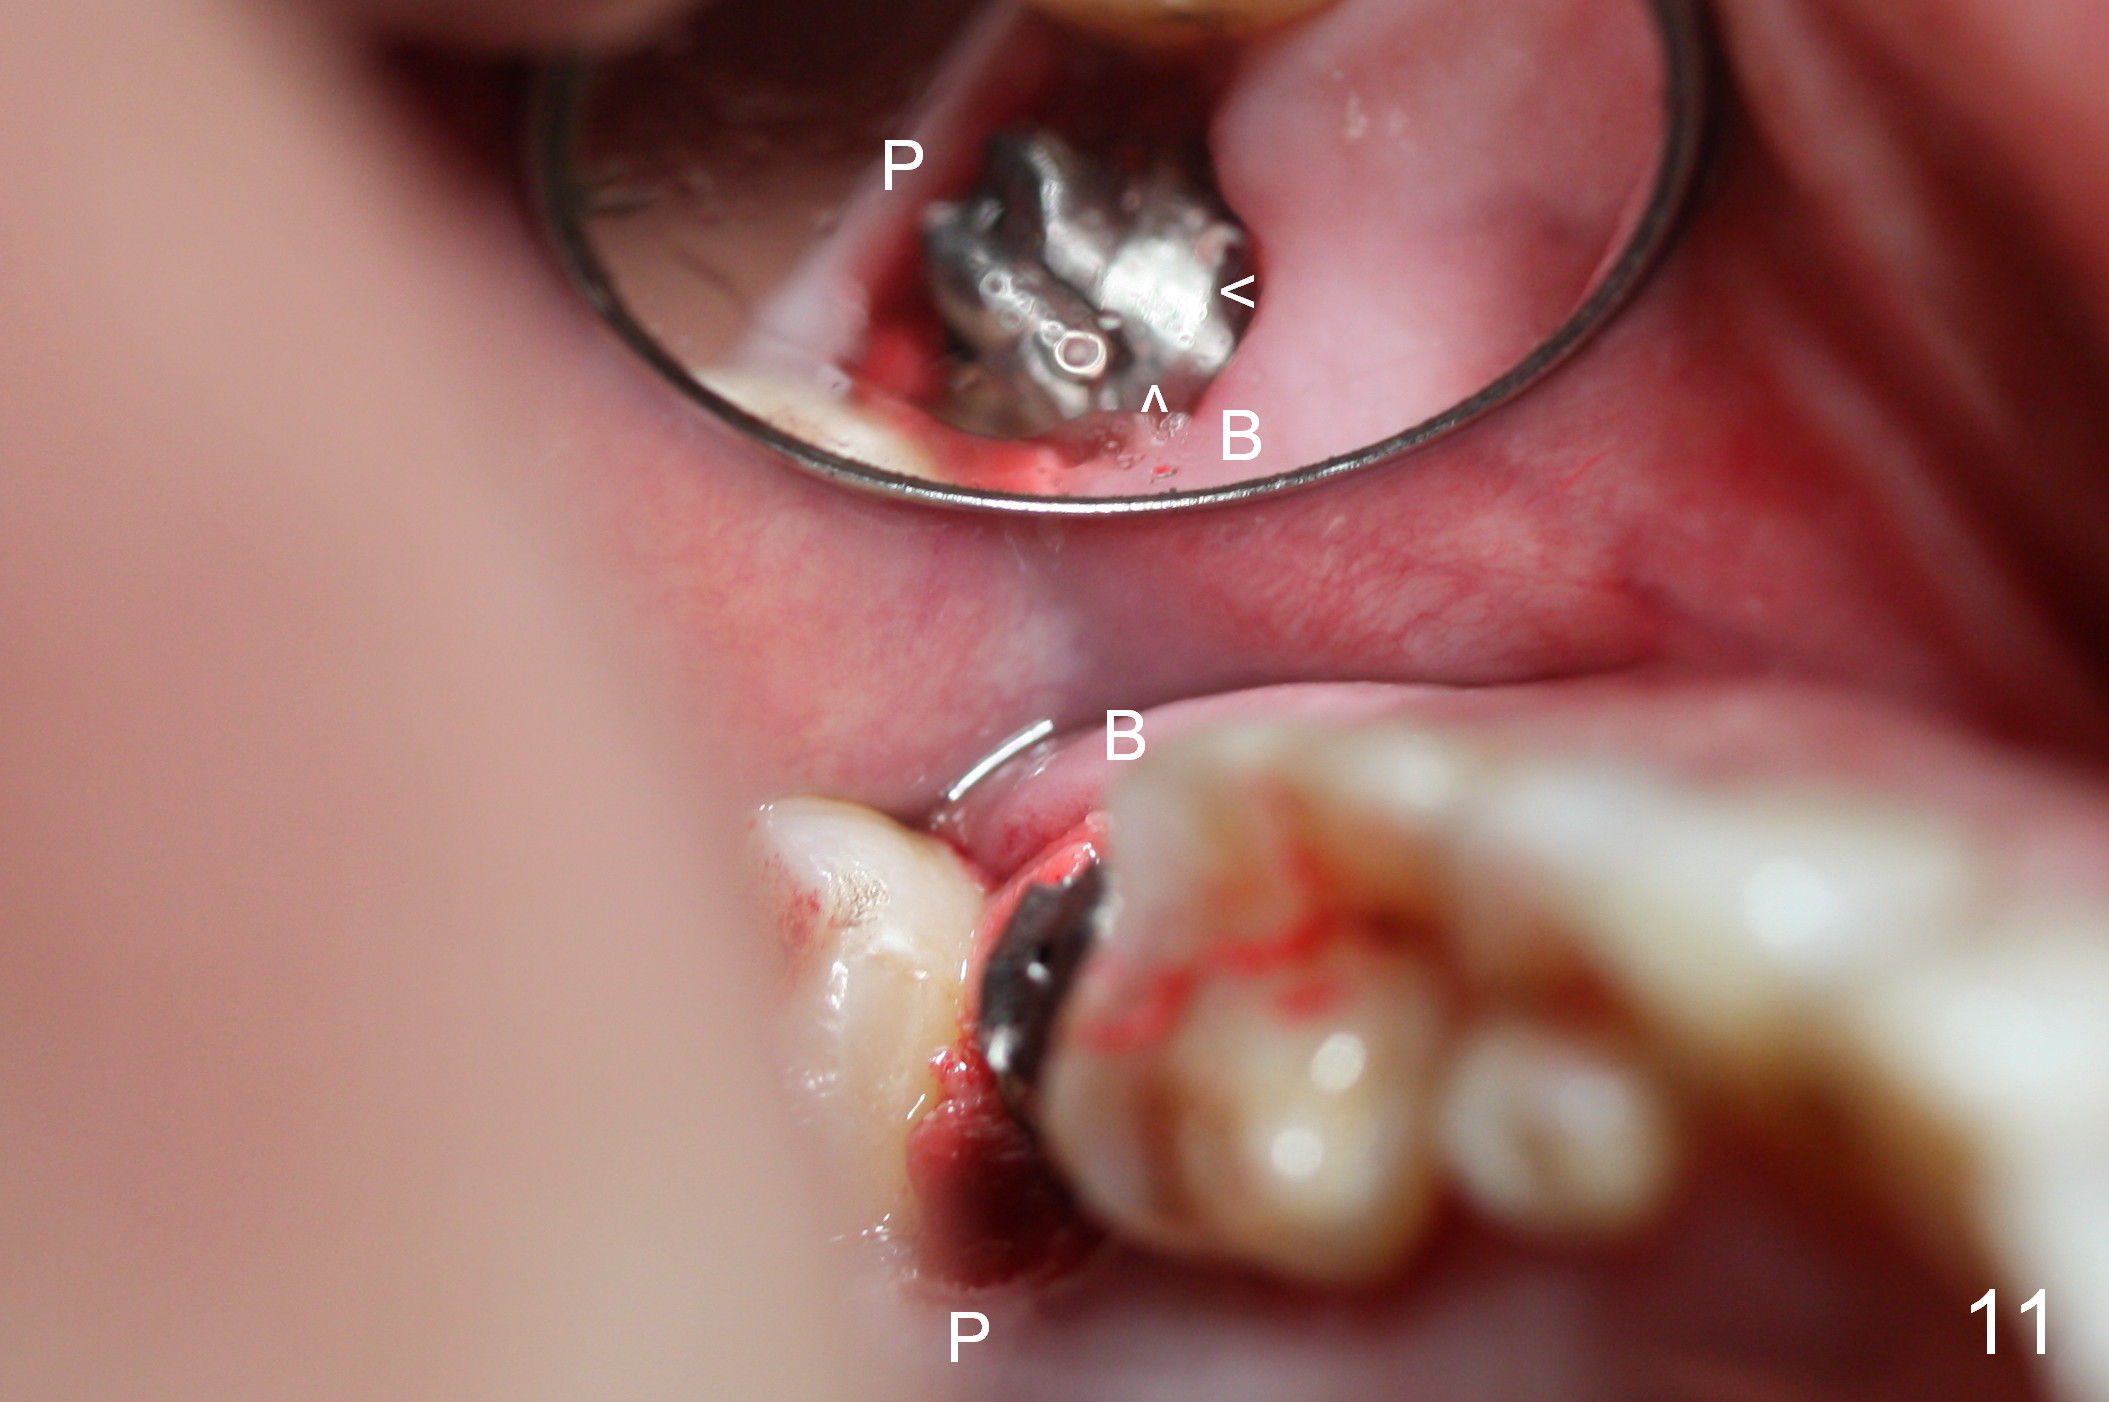

Probably due to bruxism, there is limited vertical restorative space. The margin is subgingival except buccal (Fig.10,11). An immediate provisional (Fig.12 P) appears to have to be fabricated to prevent soft tissue from covering the margin during osteointegration. It is our intention to make gingival envelop larger than the definitive crown cervix. It would be easier to remove a permanent cement later on for peri-implantitis prevention.